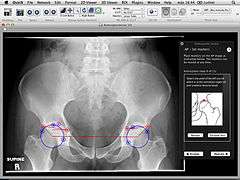

Orthopaedic Studio is an application designed to help orthopaedic specialists perform several common quantitative hip examinations that are based on standard x-ray images.

Orthopaedic Studio evaluates four different types of hip radiographs (standing anteroposterior, Von Rosen, false profile and frog). On such images a number of standardized angles, offsets and ratios can be measured, including:[1]